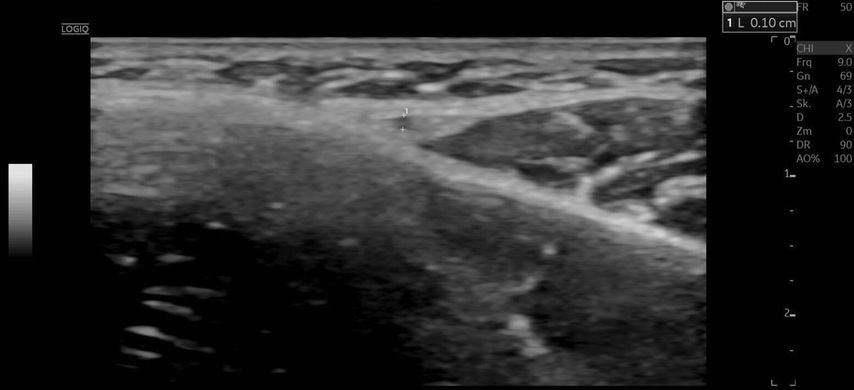

Die Duplexsonografie ergab folgende Befunde (Abb. 5 und Abb. 6):

Der Durchmesser der A. angularis und A. facialis hatte sich nahezu verdoppelt.

Die systolische Spitzengeschwindigkeit (PSV) stieg von 20cm/s auf über 100cm/s.

Die enddiastolische Geschwindigkeit (EDV) betrug nun 20cm/s, was auf eine periphere Vasodilatation und eine Wiederherstellung der Makrozirkulation hindeutete (Abb. 7).